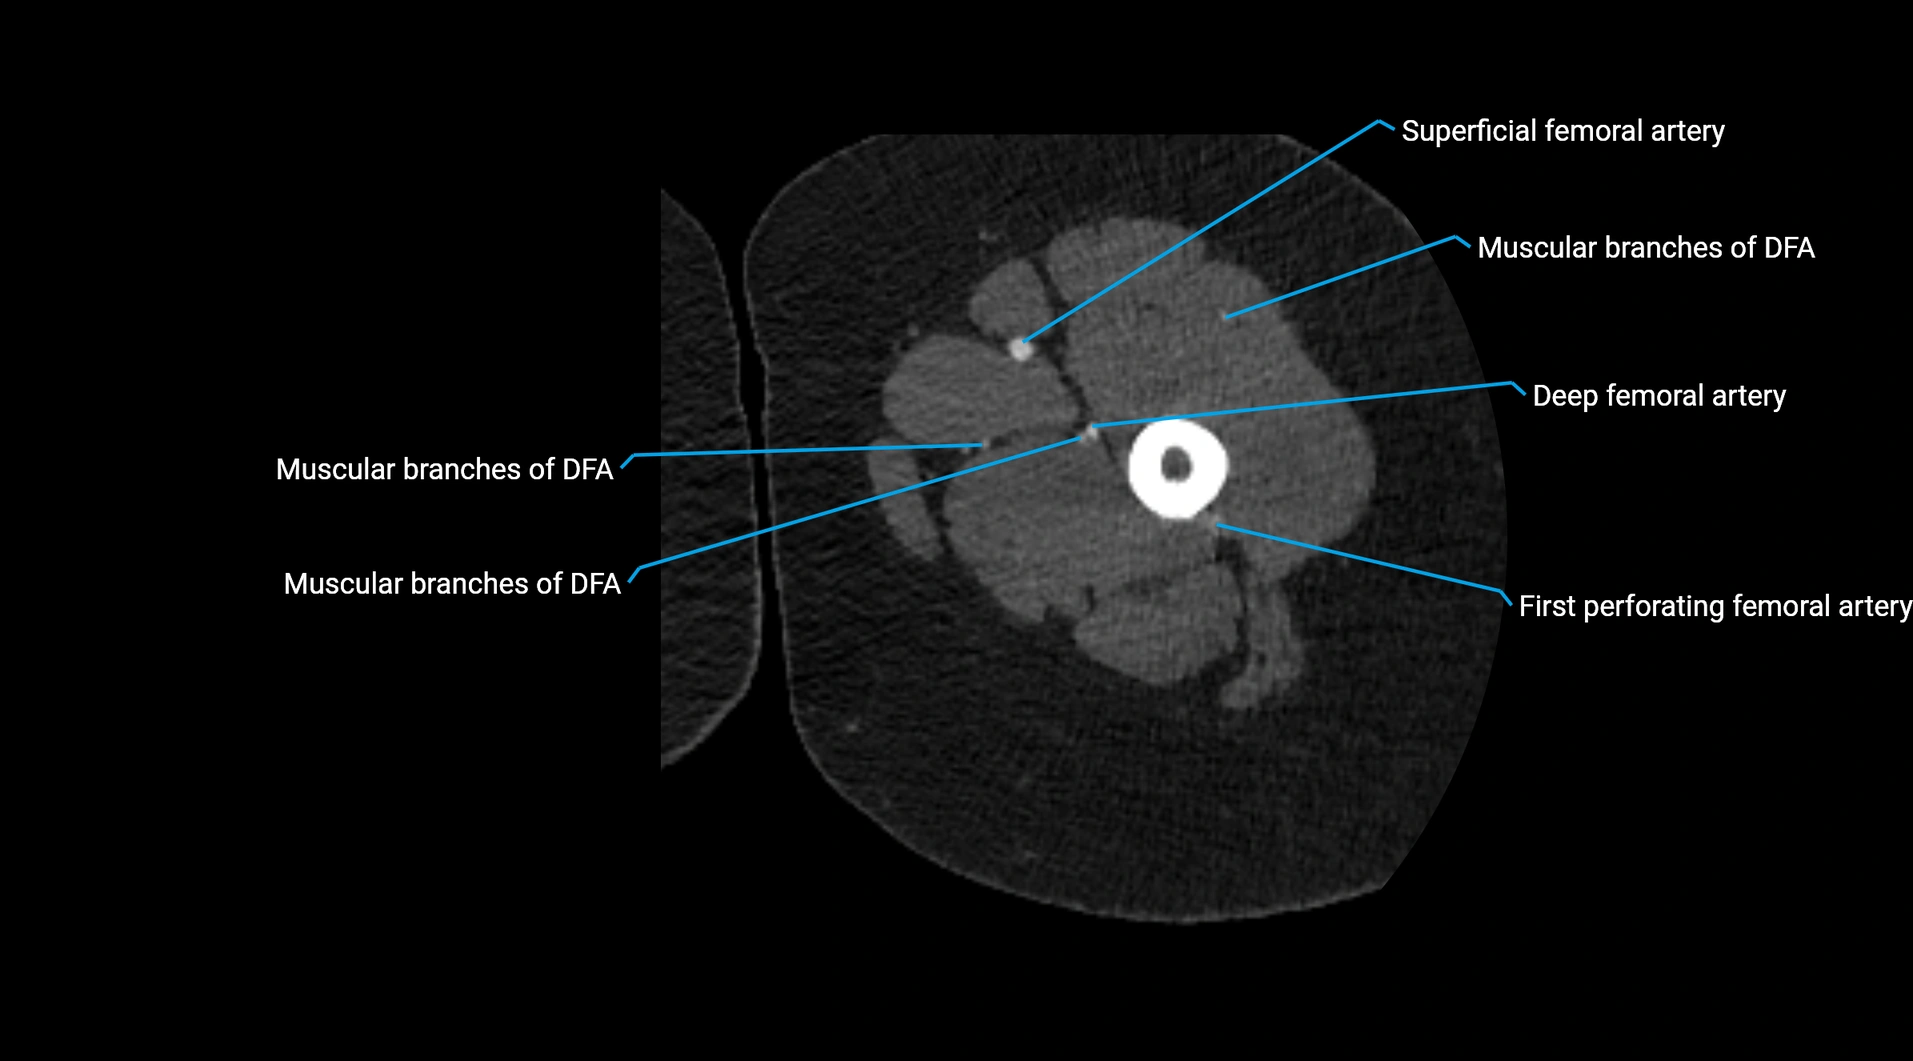

Contrast-enhanced CT (CTA):

• Gold standard for abdominal aortic imaging

• Provides excellent detail of lumen, wall, aneurysm, thrombus, and branch vessels

• Multiplanar and 3D reconstructions help in aneurysm measurement, stent graft planning, and dissection evaluation

• Detects acute rupture, traumatic injury, or occlusion with high sensitivity